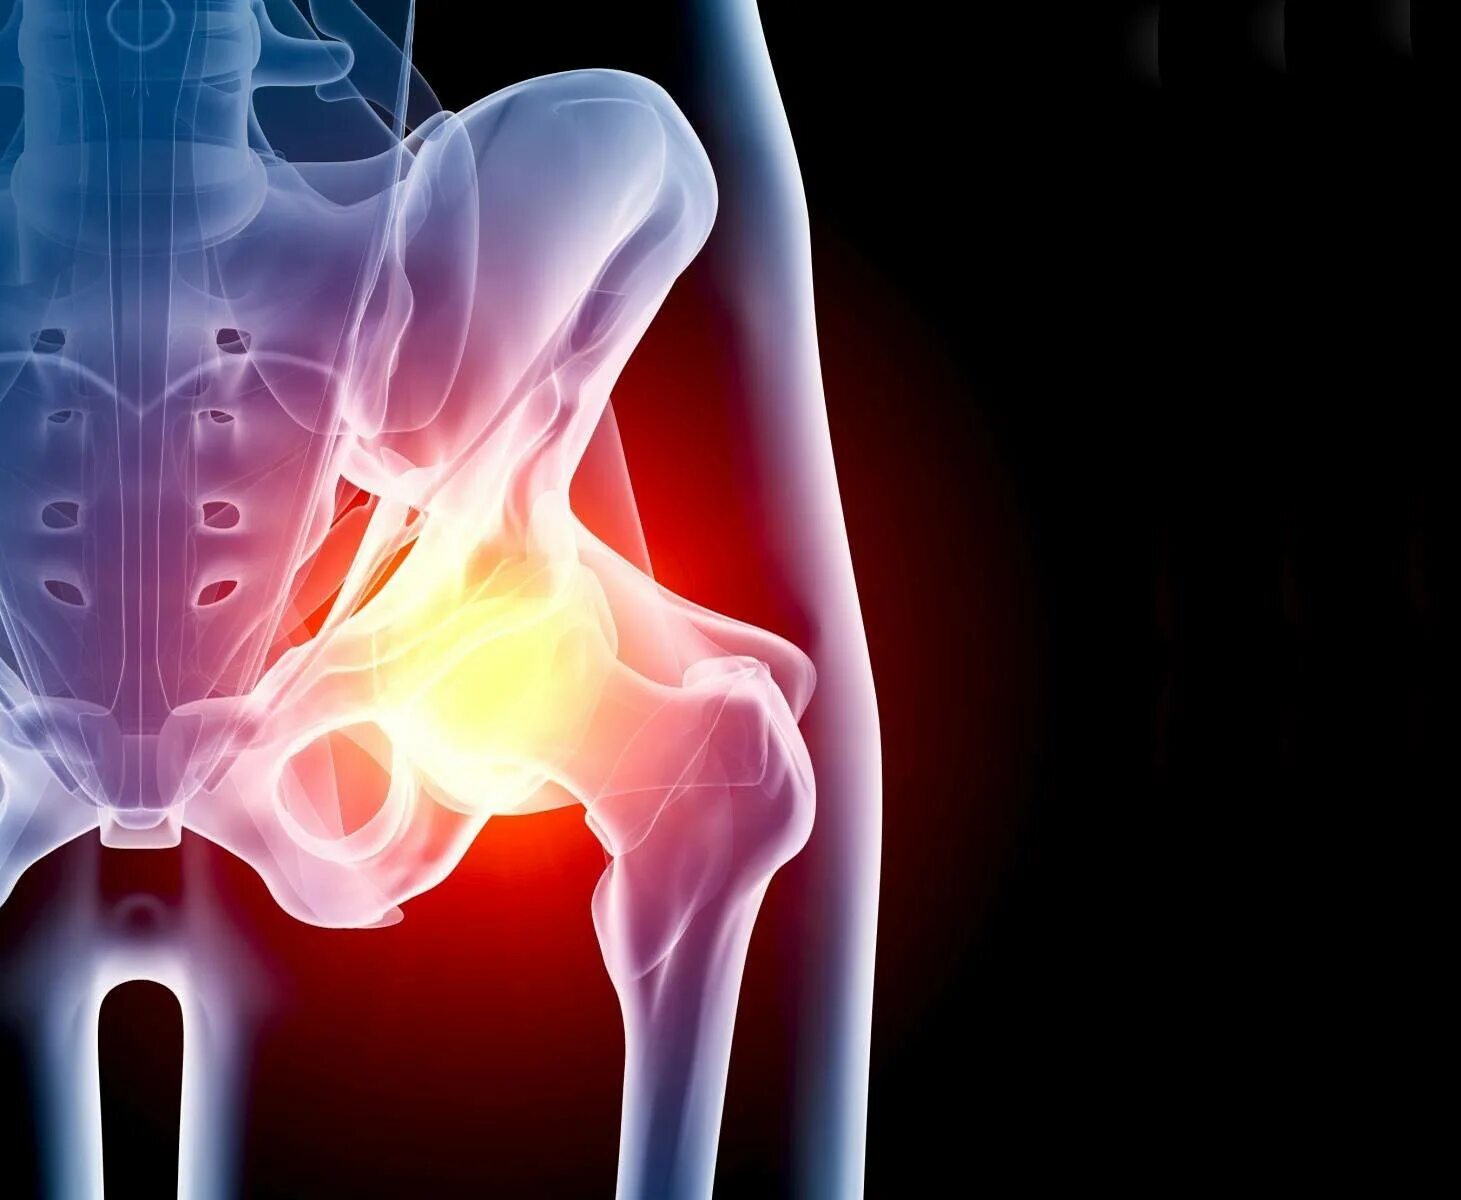

Тазобедренный сустав это